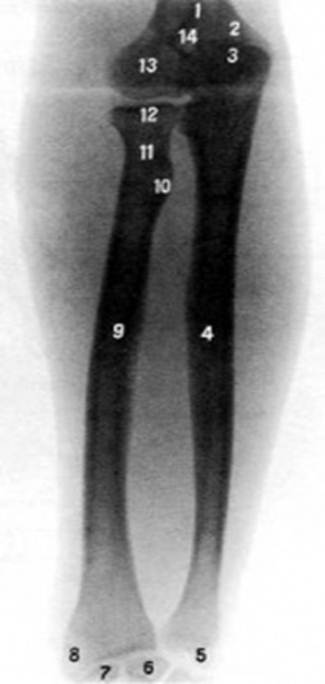

S: Цифра 9 указывает на … лучевая кость

S: Цифра 4 указывает на локтевая кость

S: На рентгеновском снимке изображен articulatio cubiti (латинский язык).